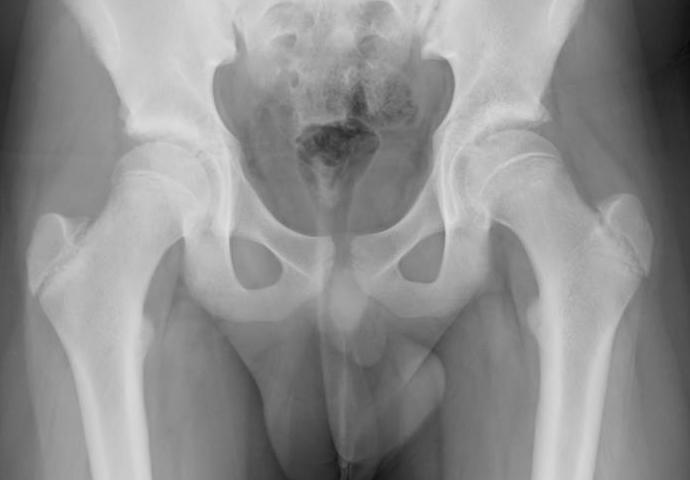

AP Xray

Widened eipiphysis

Klein's Line

- line along superior neck should transect part of epiphysis

Mild slip with failure of Klein's line to transect epiphysis